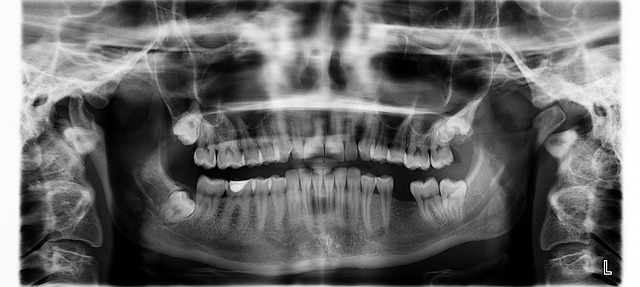

2) 충치와 잇몸 질환

이가 썩어 충치가 생기게 되면 치아에 생긴 작은 구멍에 음식물과 세균이 쌓여 입냄새를 유발합니다. 충치가 심해지면 냄새가 더욱 심해질 수 있습니다. 마찬가지로 잇몸 질환이 생겨도 세균이 번식하면서 불쾌한 냄새가 발생합니다. 이때 잇몸이 붓거나 피가 나는 증상이 함께 나타날 수 있습니다.